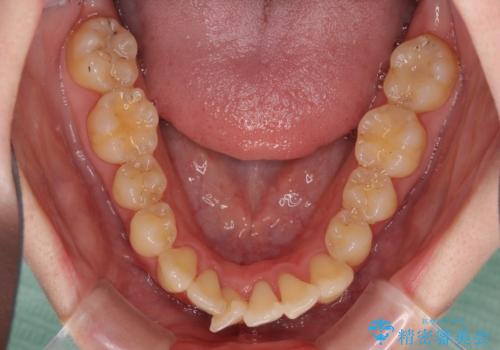

上下前歯のデコボコをきれいに インビザラインによる矯正治療

- 前歯の著しい叢生と前突感を気にして来院された患者様です。

叢生が強いため、事前に前歯をワイヤー矯正で速やかに叢生を解消し、その後はインビザラインにて矯正治療を行うこととしました。

ワイヤー矯正を併用したことで前歯の叢生を速やかに解消することができました。

一方口元の突出感を改善するために時間がかかり、2年超を要しましたが、満足のいく仕上がりとなりました。